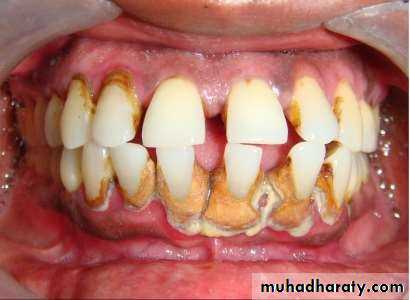

• Periodontal pockets around lower anterior teeth, showing rolled margins, edematous inflammatory changes and abundant calculus